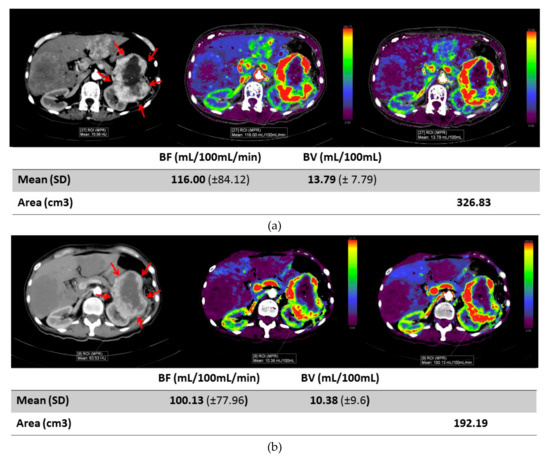

Early Changes in CT Perfusion Parameters: Primary Renal Carcinoma Versus Metastases After Treatment with Targeted Therapy

Cancers 2019, 11(5), 608; https://doi.org/10.3390/cancers11050608 - 30 Apr 2019

Computed tomography (CT) perfusion is a novel imaging method to determine tumor perfusion using a low-dose CT technique to measure iodine concentration at multiple time points. We determined if early changes in perfusion differ between primary renal tumors and metastatic tumor sites in [...] Read more.

Computed tomography (CT) perfusion is a novel imaging method to determine tumor perfusion using a low-dose CT technique to measure iodine concentration at multiple time points. We determined if early changes in perfusion differ between primary renal tumors and metastatic tumor sites in patients with renal cell carcinoma (RCC) receiving targeted anti-angiogenic therapy. A total of 10 patients with advanced RCC underwent a CT perfusion scan at treatment baseline and at one week after initiating treatment. Perfusion measurements included blood volume (BV), blood flow (BF), and flow extraction product (FEP) in a total of 13 lesions (six primary RCC tumors, seven RCC metastases). Changes between baseline and week 1 were compared between tumor locations: primary kidney tumors vs metastases. Metastatic lesions had a greater decrease in BF (average BF difference ± standard deviation (SD): −75.0 mL/100 mL/min ± 81) compared to primary kidney masses (−25.5 mL/100 mL/min ± 35). Metastatic tumors had a wider variation of change in BF, BV and FEP measures compared to primary renal tumors. Tumor diameters showed little change after one week, but early perfusion changes are evident, especially in metastatic lesions compared to primary lesions. Future studies are needed to determine if these changes can predict which patients are benefiting from targeted therapy. Full article